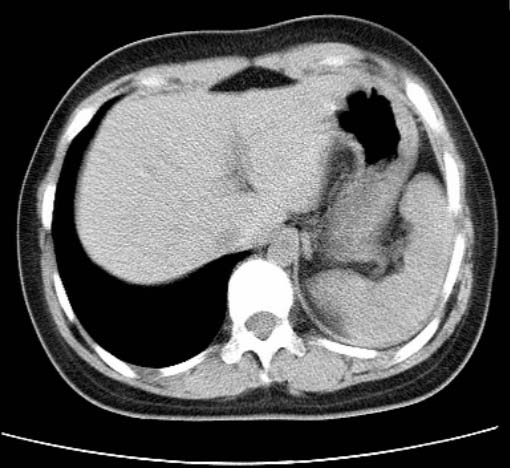

标题: CT25648:求教:是肺发育不全还是结核?

女  20岁。一月前咳血,诊“肺结核”抗痨治疗一月后,咳血停止,现复查。病人精神好。前后ct片对比未见明显变化。既往体检“正常”

1)考虑左肺结核并肺不张、支气管扩张。2)纵隔疝。

考虑左肺结核,左肺毁损,纵膈左偏,既往体检正常不可靠,tb一个月也不会这个样子的,有钙化,应该病程较长,冰冻三尺非一日之寒!

左肺发育不全。

考虑左肺结核,左肺毁损,纵膈左偏,既往体检正常不可靠,tb一个月也不会这个样子的,有钙化,应该病程较长,冰冻三尺非一日之寒

结核,左肺毁损。